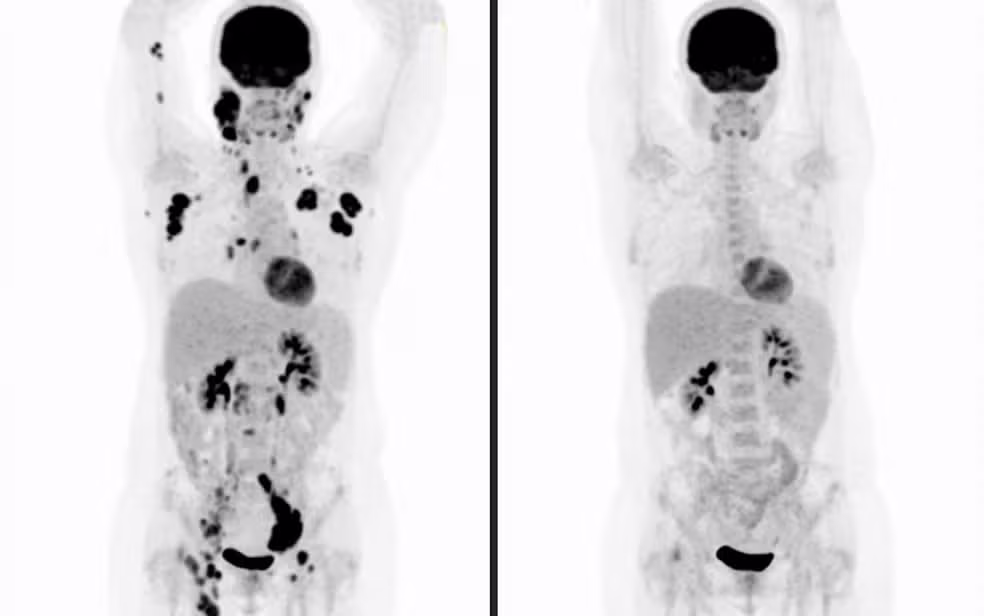

Pesquisa indica que tratamento de R$ 3 milhões apresenta superior custo-benefício na luta contra o câncer

Foto: Divulgação

O estudo, liderado pelo médico Samir Nabhan, supervisor de Transplante de Medula Óssea, Oncologia e Hematologia do Complexo Hospital de Clínicas da Universidade Federal do Paraná (UFPR), foi apresentado no Congresso Brasileiro de Hematologia, Hemoterapia e Terapia Celular. Publicado no Journal of Medical Economics, o levantamento analisou o impacto tanto financeiro quanto clínico da terapia CAR-T em pacientes com linfoma difuso de grandes células B, o tipo mais agressivo e comum de linfoma não Hodgkin.

A terapia celular CAR-T consiste em uma forma avançada e personalizada de imunoterapia. Nela, os linfócitos T, células de defesa do paciente, são removidos de seu sangue, geneticamente modificados em laboratório para atacar o câncer e infundidos novamente no organismo.

A Agência Nacional de Vigilância Sanitária (Anvisa) já aprovou a tecnologia para tratamento de linfomas e leucemias resistentes a outras terapias. Entre os produtos disponíveis estão o axi-cel, tisa-cel e cilta-cel, este último usado para mieloma múltiplo.

Antes do advento da CAR-T, a taxa de cura para o linfoma difuso de grandes células B recorrente não superava 20%. Com a nova terapia, índices de cura e sobrevida sobem para 50% a 60% em dois anos, de acordo com o levantamento.